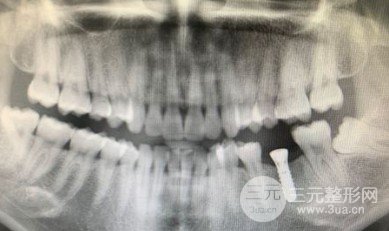

告诉大家睡前一定要刷牙,我是看着自己的牙不断的变黑,修补了一阵子以后做了烤瓷,用了三四年以后有一天肿了就去拔了。看着我其实还有个智齿要拔掉,但是我实在太害怕拔牙了,就算了再说吧,我知道等它疼了再看不好但是我还想拖一拖。